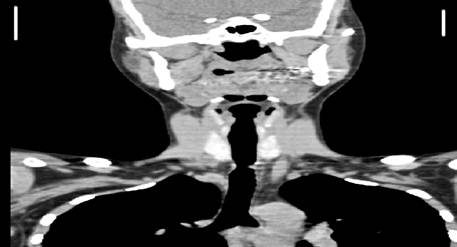

Tomografía axial computarizada: donde se constata una estenosis traqueal severa a nivel del cuerpo vertebral D-l (Fig.1 y Fig.2).

Traqueoscopia: donde se precisó la estenosis de más de un 50 % de la luz de la tráquea, a 20 centímetros de la arcada dentaria superior.